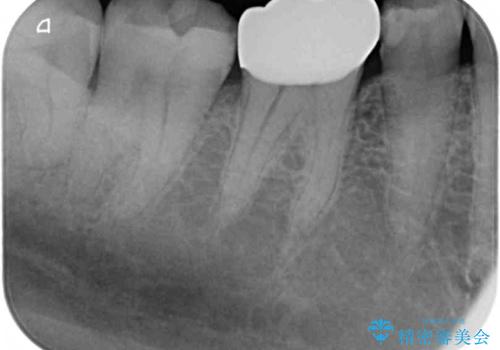

- 奥歯が欠けてしまったとのことで来院された患者様です。

おそらく歯が欠けて、装着されていた銀歯が外れてしまったと思われましたが、患者様はあまりはっきりとは覚えていないとのことでした。

咬合力が強いため、強化セラミッククラウンでの補綴治療を行うこととしました。